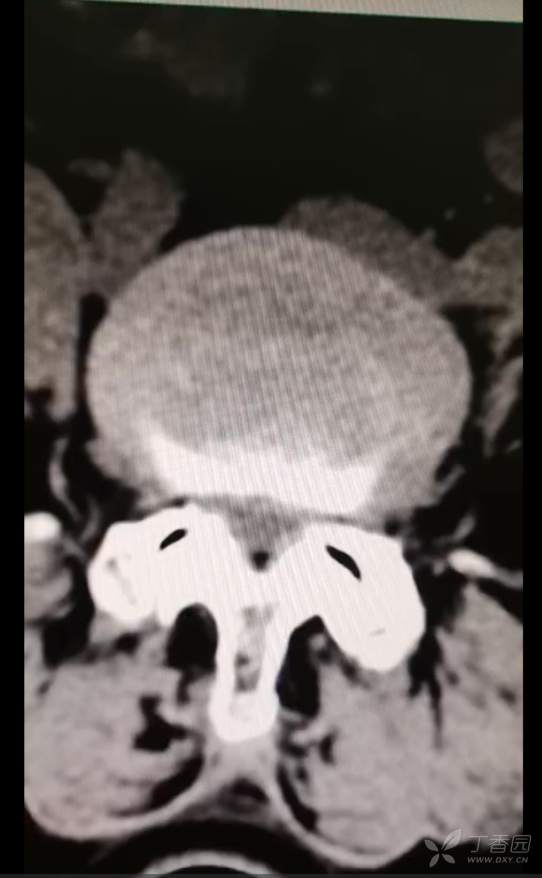

黄骨头脊柱内镜——腰4-5椎管狭窄侧路减压一例